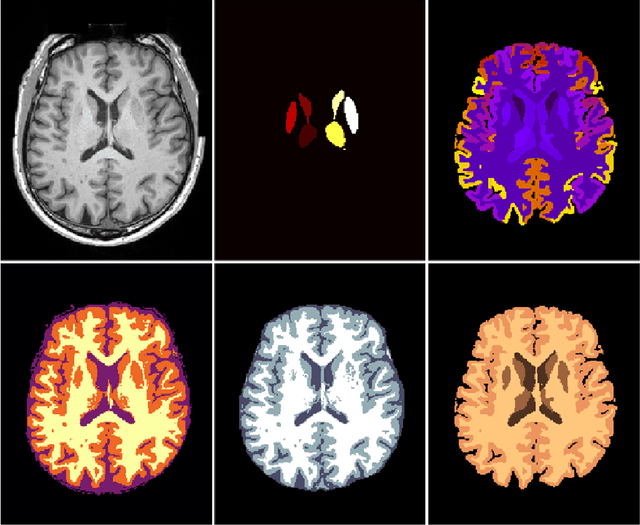

Abstract:NeuroNet is a deep convolutional neural network mimicking multiple popular and state-of-the-art brain segmentation tools including FSL, SPM, and MALPEM. The network is trained on 5,000 T1-weighted brain MRI scans from the UK Biobank Imaging Study that have been automatically segmented into brain tissue and cortical and sub-cortical structures using the standard neuroimaging pipelines. Training a single model from these complementary and partially overlapping label maps yields a new powerful "all-in-one", multi-output segmentation tool. The processing time for a single subject is reduced by an order of magnitude compared to running each individual software package. We demonstrate very good reproducibility of the original outputs while increasing robustness to variations in the input data. We believe NeuroNet could be an important tool in large-scale population imaging studies and serve as a new standard in neuroscience by reducing the risk of introducing bias when choosing a specific software package.